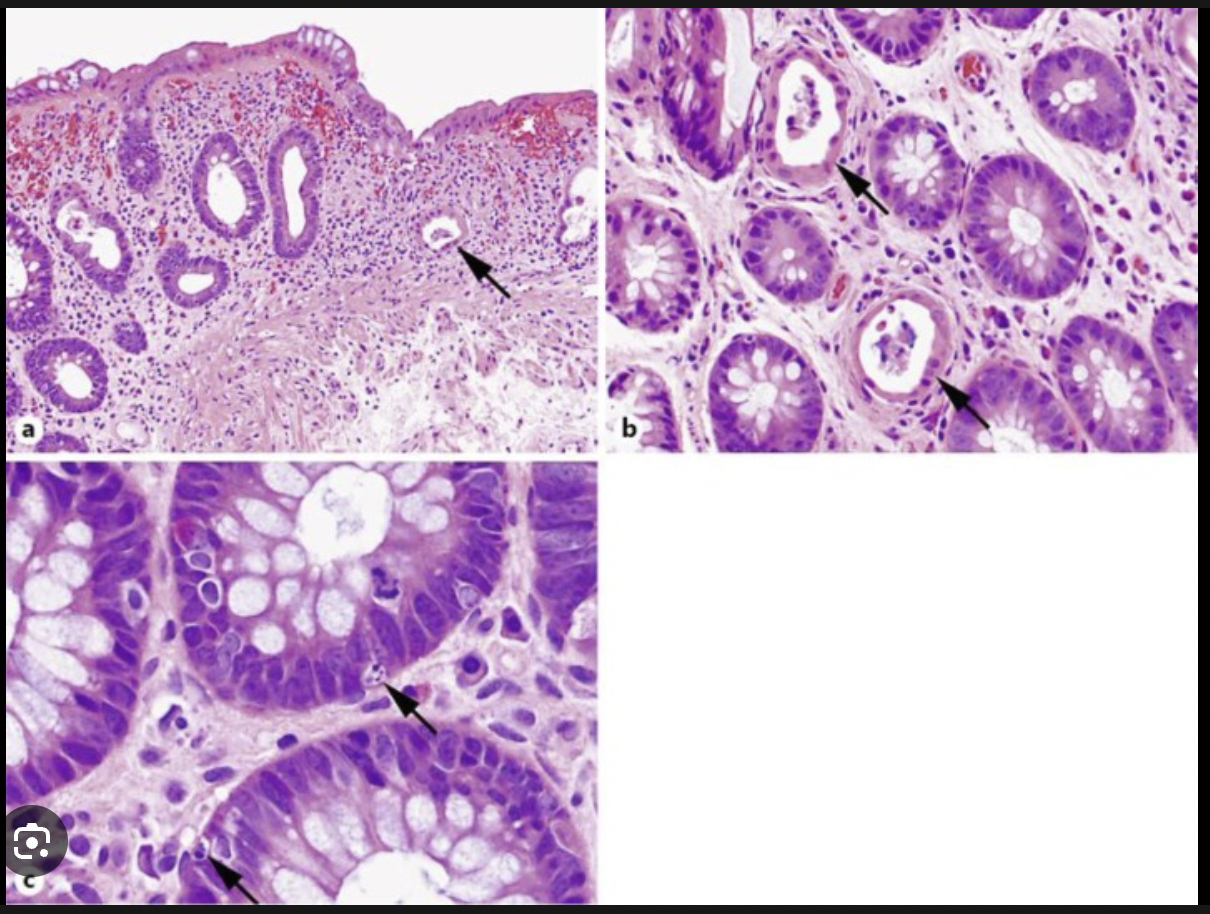

Colon biopsy

low grade dysplasia

Chronic colitis

altered crypt architecture (branching crypts)

microabcesses